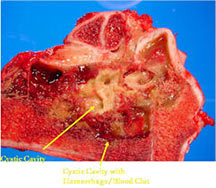

- Telangiectatic osteosarcomas have a variable gross appearance

- They may appear as a large blood clot filling a single large cystic cavity; hemorrhagic and necrotic mass; or a multicystic fluid-filled lesion

- Thin septae exist between the cystic cavities that harbor malignant appearing spindle cells producing scant osteoid

- Its gross appearance can mimic an aneurysmal bone cyst

- Mixture of large cystic and spongy areas